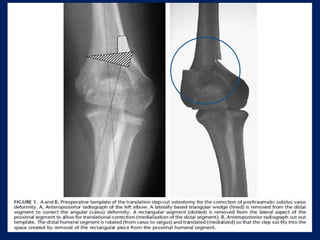

Step Cut Osteotomy(DeRosa and Graziano)  A standard posterior approach used.  Incision extended proximally from distal 3rd upper arm to a distance of 1 to 2 cm beyond the tip of the olecranon distally.  mobilize the ulnar nerve anteriorly.  The triceps muscle was then split longitudinally.  Circumferential subperiosteal dissection done.

• 45.

 The osteotomywas performed by first making a proximal, transverse cut perpendicular to the anatomical axis of the humerus.  Then, the angular correction cut was made based on the degree of correction desired, as determined from the preoperative planning template.  cut was made in a proximal-medial to distal- lateral direction.  next cut, perpendicular to the angular correction cut was made at its lateral margin, creating a step cut in the distal humeral fragment.

 Once thesesteps were completed, the proximal and distal segments were aligned and the clinical carrying angle reassessed.  Internal fixation was achieved by placing two 1.6mm k-wires through the lateral epicondyle and 1 k-wire through the medial epicondyle.